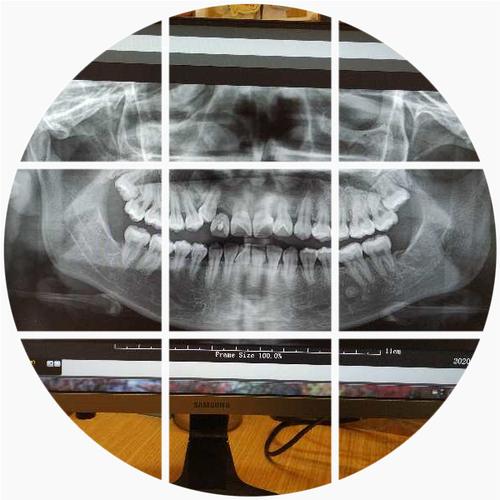

nobel种牙有风险吗

任何一种手术,都是存在风险的。Nobel的系统是成熟的,然而要是医生在术前评估的时候做得不够到位,举例来说,骨量不足却强行进行操作、位置设计出现偏差,那么也有可能出现神经受到损伤、种植体遭遇失败这一类的情况。除此之外,还存在着一个隐性的风险,那就是后期配件匹配方面的问题。Nobel的配件属于封闭系统,要是诊所在后期不备货或者医生并不熟悉,那么在维修更换之际就会比较麻烦。选择医生相较于选择植体而言是更为重要的,具备经验的医生能够把风险降低到最低限度。